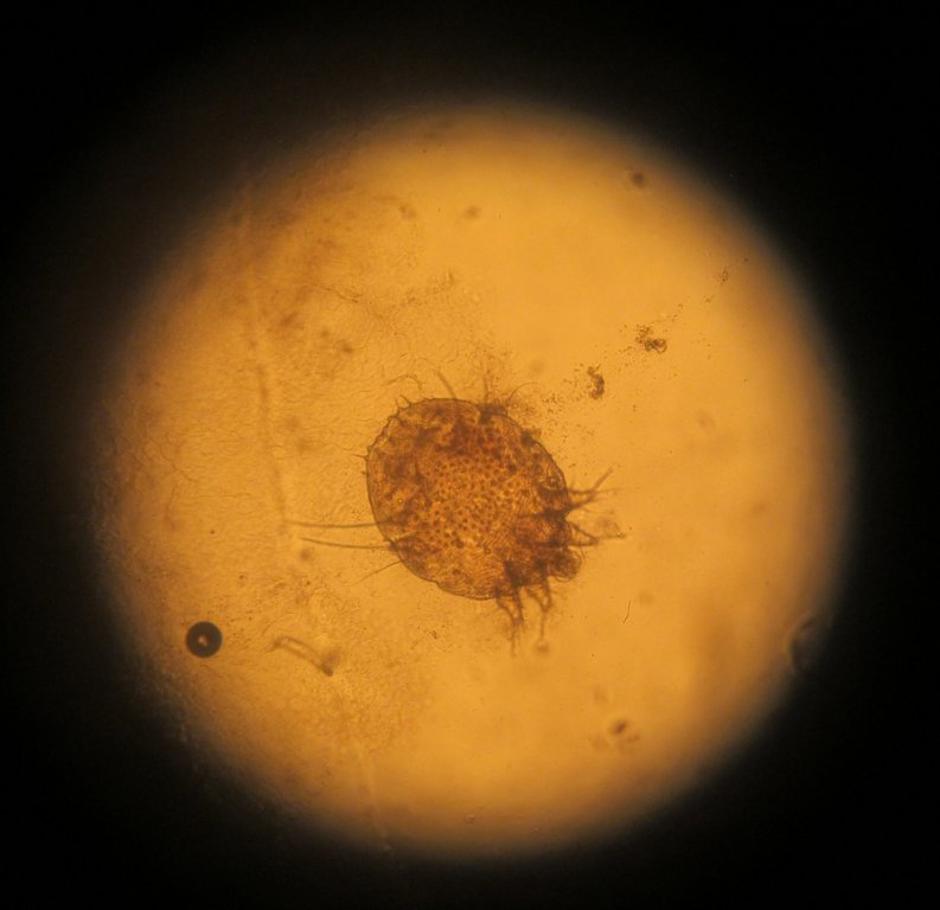

Garje ali srbečica je kožna nalezljiva bolezen, ki jo povzroča pršica, ki predvsem v nočnem času vrta rovčke v povrhnjo plast kože ter vanjo leže jajčeca. Posledica tega so spremembe na koži v obliki drobnih rožnatih papul velikosti prosa, s krastico na vrhu, ki močno srbijo.

| Avtor: Nijz Nijz